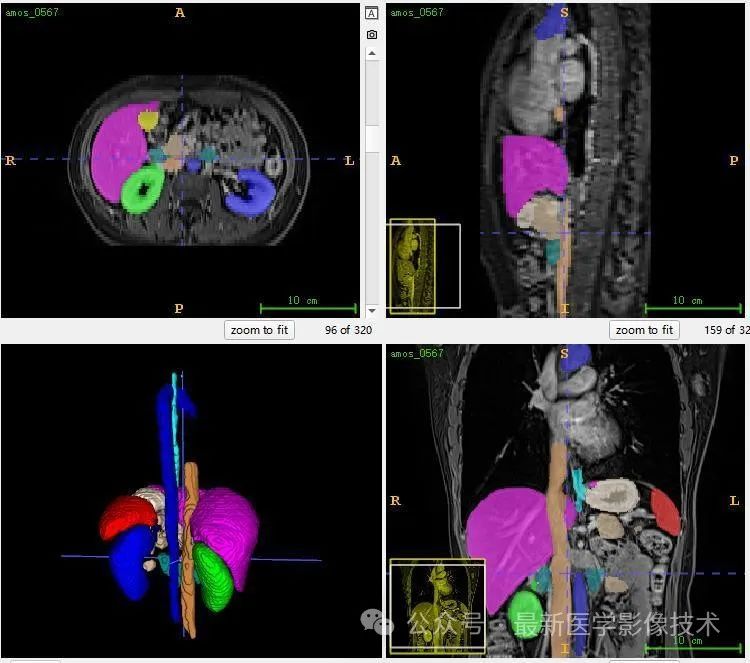

12、验证集分割结果

左图是金标准结果,右图是预测结果。

13、测试集分割结果